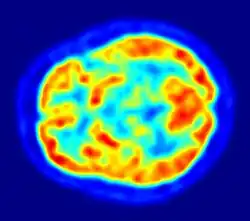

A cintilografia, cintigrafia, gamagrafia, cintilograma ou cintigrama é um método de diagnóstico por imagem da Medicina Nuclear. Na tela no computador, são geradas fotos ou filmes da distribuição de um radiotraçador (também referido de radiomarcador) injetado no paciente que podem ser analisadas da forma visual ou quantitativa através de cálculos da concentração e velocidade de movimento desse radiotraçador.

Neste exame são formadas primariamente imagens funcionais (vê a função dos órgãos) em contraste com a radiologia geral em que são formadas imagens anatômicas (vê a forma dos órgãos). O radiotraçador (ou radiofármaco) é geralmente a união de um radioisótopo (átomo emissor de onda eletromagnética do tipo raio gama que é o sinal para formação da imagem) com um análogo de uma molécula fisiológica (traçador que é escolhido de acordo com o órgão e função a ser estudada). A radiação gama é uma onda eletromagnética semelhante à luz visível, porém seu "brilho" ou cintilação é apenas visto através de uma máquina chamada câmara gama, um detector a cintilação, que nos permite a visualização de imagens dos órgãos internos.